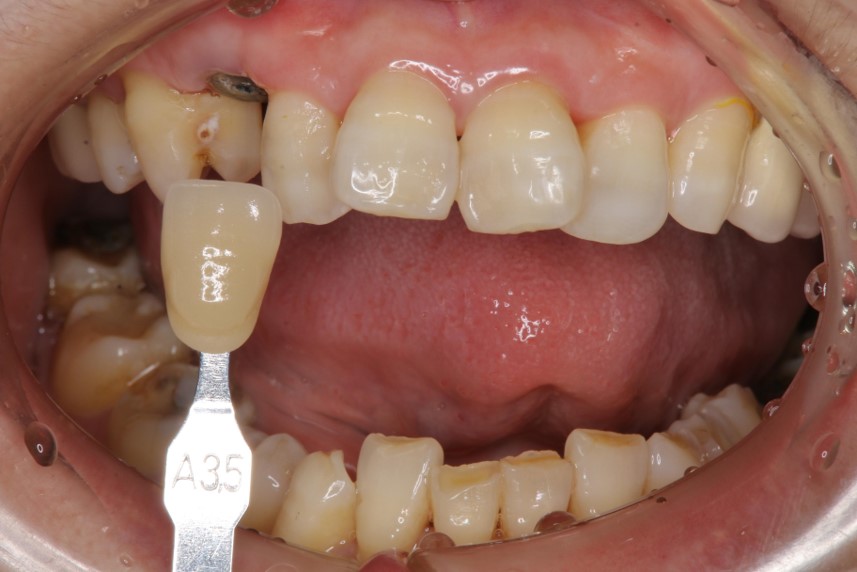

照相比色